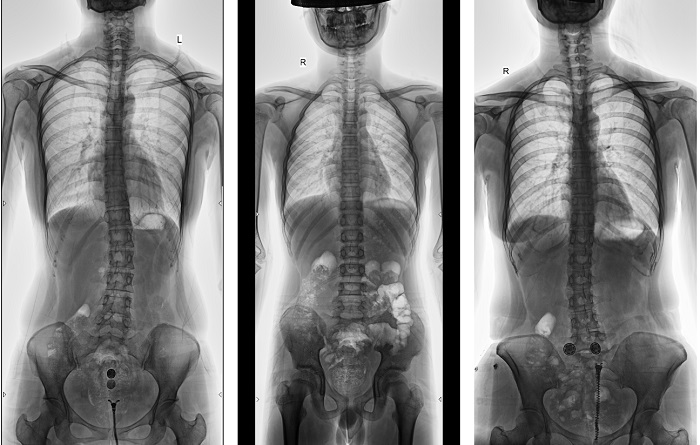

動態DR全景拼接功能突破平板尺寸長度限制,可進行立臥位攝影,對脊柱、下肢及下肢靜脈造影進行分段攝片,然后對分段圖像進行拼接,在一幅X光圖像上完整顯示全脊柱或下肢整體形態,獲得全脊柱或全下肢圖像,有效解決了傳統X光片不能一次成像問題,通過直觀顯示脊柱和下肢的整體解剖形態及側凸部位,為臨床治療提供重要參考依據。

▲全脊柱DR影像

普利德多功能動態DR進行全脊柱全下肢圖像拼接時,影像密度均勻、清晰、接緣處過渡自然,圖像質量高,完全能滿足臨床觀察、診斷及測量要求。拍片過程也更加方便快捷,使患者得到快速診斷,及時治療,為臨床醫生和患者帶來更大的便利,大大助力醫院醫療服務能力的提升!